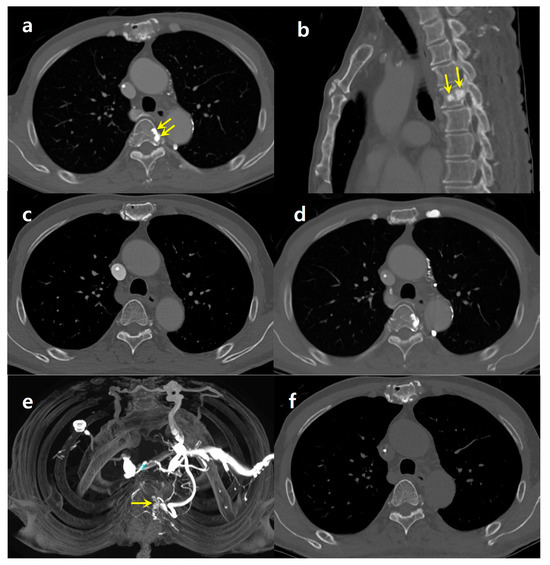

A 69-year-old male patient, who had undergone a radical cholecystectomy for gallbladder cancer seven years earlier, was under continuous surveillance for potential metastasis following his surgery and subsequent adjuvant concurrent chemoradiation therapy. As part of his ongoing monitoring, he recently underwent a contrast-enhanced chest CT scan. In this particular scan, the contrast agent was administered through his left antecubital vein. The chest CT images revealed a focal sclerotic lesion at the left lateral aspect of the T4 vertebral body (Figure 2a,b). Notably, this lesion had not been visualized in the CT scan obtained three months earlier, which had involved contrast injection through his right arm (Figure 2c). The imaging studies, including CT scans, ultrasonography, and angiography performed during chemoport insertion, showed no evidence of deep venous obstruction.

Upon reviewing the patient’s imaging history at our institution, it was found that he had undergone a total of 13 chest CT scans. Interestingly, a sclerotic area was consistently observed at the same location in the CT scans where the contrast was injected from the left side (Figure 2d). However, the seven chest CT scans obtained with right-side contrast injection did not reveal any focal sclerotic lesions in the vertebrae. A maximum-intensity projection reconstruction of the contrast-enhanced CT scans demonstrated focal enhancement at the T4 vertebra, which was attributed to the flow through the paravertebral venous plexus (Figure 2e). This enhancement was not present in the unenhanced follow-up CT images (Figure 2f), indicating that the phenomenon was likely related to the distribution of the contrast agent.

Figure 2. A 69-year-old male with gall bladder cancer. (a) An axial contrast-enhanced chest CT image with left-side contrast injection reveals a focal sclerotic area on the left side of the T4 vertebral body (arrows). A chemoport catheter is inserted in superior vena cava. (b) Sagittal reformatted image shows nodular sclerotic foci at T4 (arrows). (c) Chest CT image obtained three months ago with right-side injection does not show the sclerotic lesion. (d) Chest CT image obtained six months ago with left-side contrast injection shows a focal sclerotic area in the same location. (e) Maximum-intensity projection (MIP, d) image from enhanced CT with left-side injection demonstrates a focal enhancing area at T4 (arrow), with the surrounding vertebral venous plexus opacified through reflux from the left brachiocephalic vein. Collateral flows are also noted in both internal mammary and left superior intercostal veins. (f) A follow-up chest CT with contrast injection through his right arm showing no evidence of a sclerotic lesion in T4 or paravertebral venous collaterals.